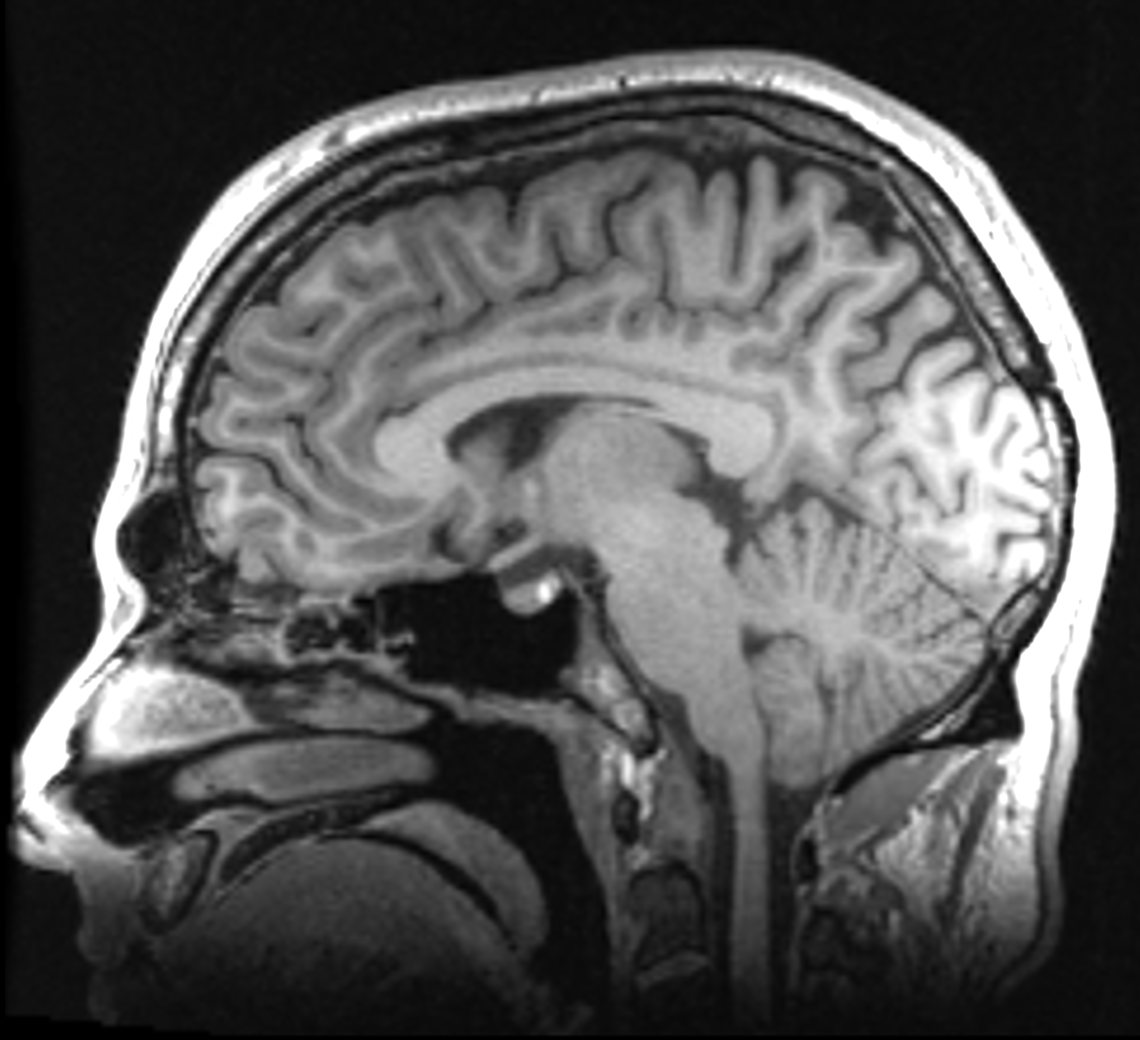

In this study, we use magnetic resonance imaging (MRI) to assess brain metabolites associated with pain and knee health. MRI is non–invasive and does not use ionizing radiation. Knee MRIs are being acquired to best show the structural damage as we expect they will provide more information for research purposes than clinical x-rays. Brain imaging is being acquired to examine differences in the brain that occur with chronic knee osteoarthritis pain (or its recovery) We expect this combined information will provide great insight to knee osteoarthritis pain.

In this study, we are interested in learning more about why some children and adolescents experience recurrent migraines. We are studying this by using Magnetic Resonance Spectroscopy to measure metabolite levels in the brain and how these may be related to migraine. Recruitment for this study is through the Alberta Children's Hospital Headache Clinic.